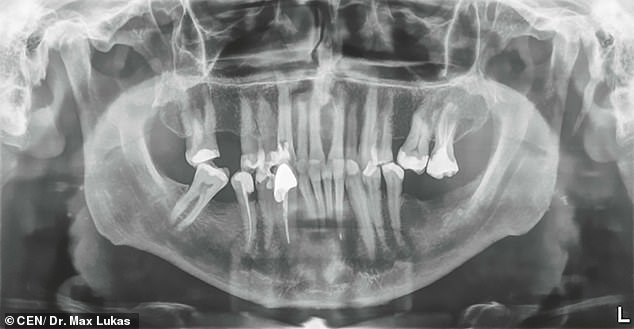

Dhererka iligta ayaa lagu sheegay 1.46 inches oo u dhiganta 3.72cm, waxaa laga saaray bukaan ka cabanayay xannuun darran.

Dr Max Lukas oo ka shaqeeya meel ku dhaw Frankfurt ayaa ku guuleystay howlgalka looga saaray dhibbanaha iligta ugu dheer caalamka.

Dhaqtarka ilkaha ayaa daweeyay Mijo Vodopija bishii September. Raajada ayaa muujisay in ninka reer Croatia uu leeyahay ilig dheer oo aan caadi aheyn islamarkaana ku sababeysa xannuun darran.